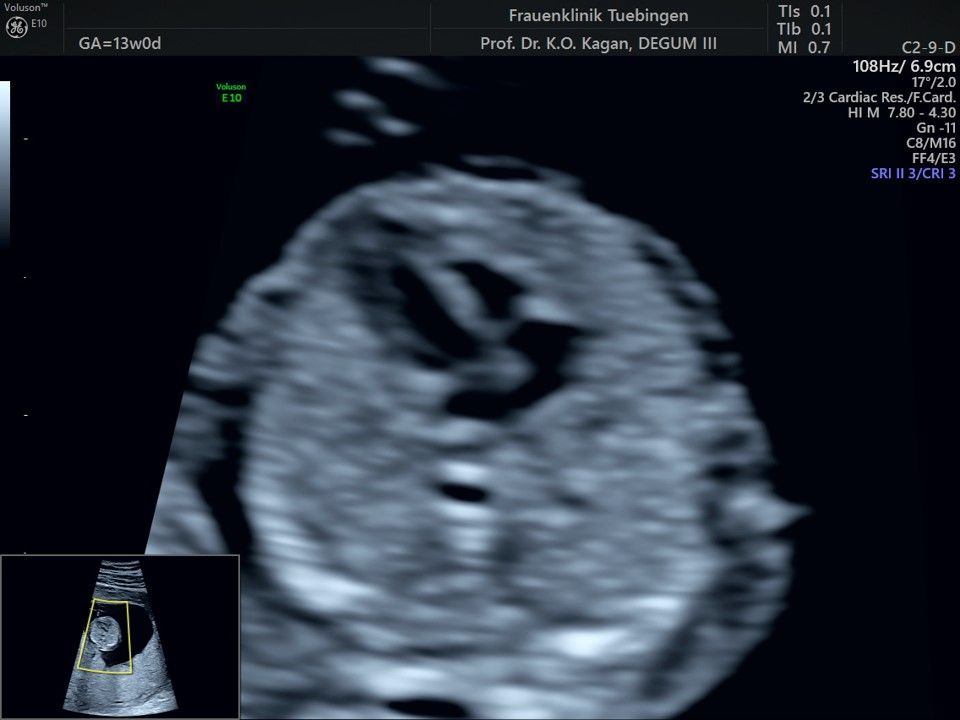

Im Rahmen des Ersttrimester-Screenings untersuchen wir die Organe des Feten mittels Ultraschall. Dabei machen wir auch gerne ein Bild für Sie.

Obwohl der Fet zu diesem Zeitpunkt erst zwischen 5 und 8cm groß ist, lassen sich bereits etwa die Hälfte aller schwerwiegenden Fehlbildungen erkennen bzw. ausschließen. Sollten wir eine Auffälligkeit sehen, werden wir mit Ihnen den Befund und das weitere Vorgehen ausführlich besprechen.

Fetale Anatomie